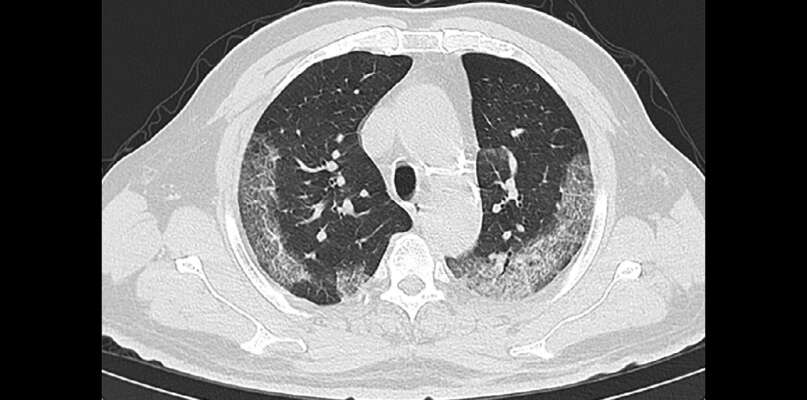

El Centro para el Control y Prevención de Enfermedades, (CDC por sus siglas en inglés), y el American College of Radiology (ACR), establecieron que no recomiendan el uso de placa de pecho o CT (Computerized Tomography) para el diagnóstico de COVID-19, así lo confirmó el jueves el doctor Gory Ballester, radiólogo certificado y presidente de la Sociedad Radiológica de Puerto Rico y del ACR, capítulo de Puerto Rico.

“La prueba de laboratorio para el COVID-19 es la única que es específica para su diagnóstico. Un CT o placa de pecho no sustituye de ninguna manera la prueba de laboratorio. Con el CT se ve si hay enfermedad en el pulmón o pulmonía en general, pero la causa especifica no se puede diagnosticar”, indicó en comunicación escrita el doctor Guido Santacana Laffitte, radiólogo certificado, especialista en imágenes de pecho.

“La confirmación del virus con la prueba de laboratorio es requerido, no importa que la placa de pecho o el CT sean sugestivos para COVID-19. Sabemos que no hay cura hasta el momento, pero es sumamente importante saber quién tiene y no tiene la enfermedad en cuanto a la salud pública del país. De esta manera, se pueden tomar las medidas necesarias para tratar y aislar aquellos que tienen la enfermedad, protegiendo al resto de la población”, añadió el doctor Ballester.

“Por tal motivo, es importante tener acceso a la prueba de laboratorio para el diagnóstico del COVID-19. El CT se debe utilizar con cautela y ser reservado para pacientes hospitalizados con indicaciones específicas para CT”, concluyó el doctor Santacana Laffitte.